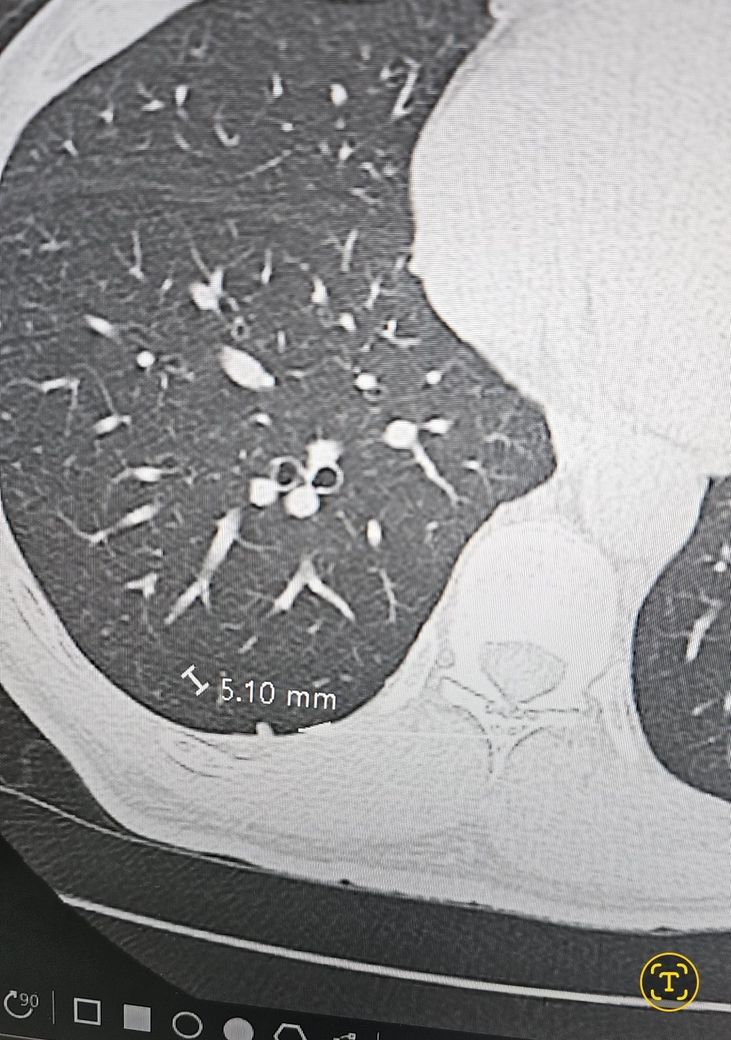

폐ct에서 결절이 나왔는데 괜찮을까요?

결절 0.51mm 있다고하는데

• 폐에 결절이 있을 경우에는 추적관찰의 대상이 됩니다. 그 크기가 지속적으로 커지고 또 너무 큰 경우에는 조직검사를 통해서 폐암 여부를 감별해보는 과정이 필요합니다. 현재 5mm 정도의 크기는 아주 큰 크기는 아니며 추적관찰을 하면서 경과를 지켜보는 정도의 크기가 되겠습니다. 반드시 빠르게 꼭 찍어보아야 할 것으로 보이지는 않습니다. 기침의 원인이 폐의 결절에 의한 것인지는 미지수이며 보통은 결절이 있어도 무증상입니다.